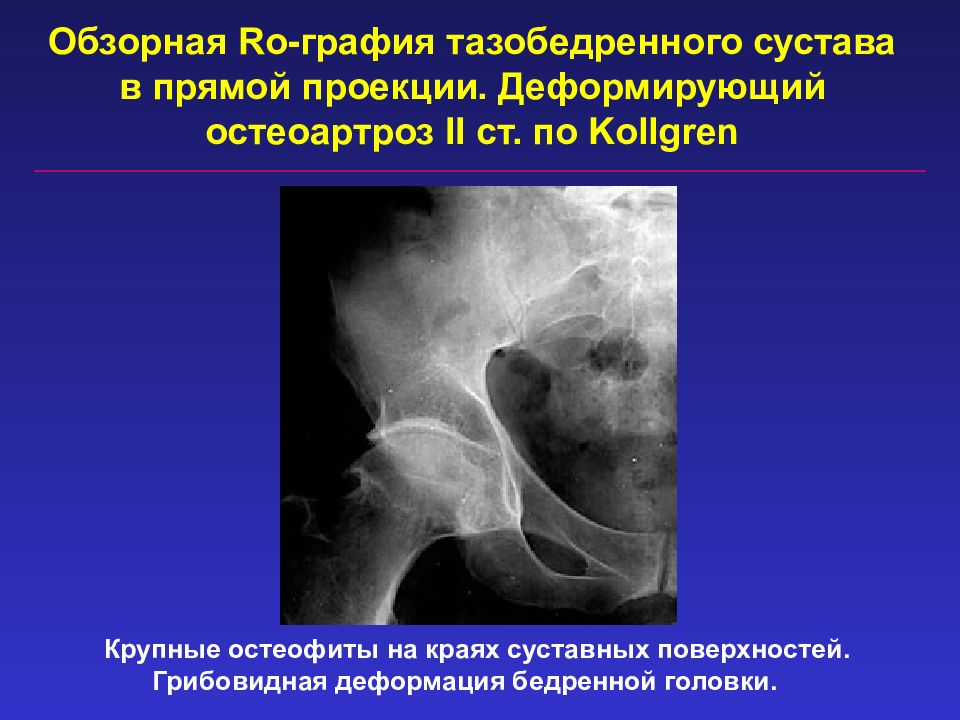

На рентгенограммах тазобедренный сустав сохраняет нормальную форму, суставная щель умеренно или неравномерно сужена с субхондральным склерозированием костных суставных поверхностей, непостоянными краевыми костными разрастаниями (I стадия).

Рентгенологически суставная щель может быть равномерно или неравномерно сужена, ацетабулярная суставная впадина уплощена, присутствуют явления субхондрального склероза, краевые костные разрастания. Конфигурация головки бедренной кости, как правило, не нарушена (II стадия).

В подавляющем большинстве случаев диагноз коксартроза ставится при рентгенографии, где видны изменения формы и структуры костей, составляющих тазобедренный сустав. Однако рентгенографически в ряде случаев затруднительно зафиксировать ранние проявления артроза, так как хрящевая ткань суставных поверхностей на рентгеновских снимках не отображается и мы можем судить о дегенеративном процессе, когда он достаточно выражен, вызывая изменения ширины просвета рентгеновской суставной щели.

Остеофиты тазобедренного сустава даже на стадии запущенного коксартроза при визуальном обследовании не видны, поскольку сустав . Как лечить. Остеофиты склонны увеличиваться, если ничего не менять в распорядке дня, питании, уровне. Остеофиты тазобедренного сустава – это костные разрастания, которые препятствуют свободной подвижности нижней конечности, провоцируют развитие болевого синдрома. Патология развивается постепенно и имеет сложную природу. Сначала происходит постепенная деформация хрящевой ткани. Лечение остеофита тазобедренного сустава должно быть комплексным. Вследствие повреждения и уменьшения протеогликанов хрящ подсыхает, становится менее насыщенным водой. Остеофиты – патологически нарост на поверхности костной структуры, который возникает вследствие нарушения метаболизма кальция или заболеваний различной этиологии. 11 Остеофиты тел позвонков: что это такое. 12 Костные наросты тазобедренного сустава. 13 Что такое костные образования. . Остеофиты – это образования, которые могут развиваться, как после непосредственного повреждения костей, так и возникать на фоне тяжелых хронических заболеваний. Какое лечение поможет избавиться от остеофитов тазобедренного сустава? Диагноз коксартроз ставится на основании совокупности клинических симптомов и рентгенологических признаков.

Остеофиты склонны увеличиваться, если ничего не менять в распорядке дня, питании, уровне. Остеофиты тазобедренного сустава – это костные разрастания, которые препятствуют свободной подвижности нижней конечности, провоцируют развитие болевого синдрома. Патология развивается постепенно и имеет сложную природу. Сначала происходит постепенная деформация хрящевой ткани. Лечение остеофита тазобедренного сустава должно быть комплексным. Вследствие повреждения и уменьшения протеогликанов хрящ подсыхает, становится менее насыщенным водой. Остеофиты – патологически нарост на поверхности костной структуры, который возникает вследствие нарушения метаболизма кальция или заболеваний различной этиологии. 11 Остеофиты тел позвонков: что это такое. 12 Костные наросты тазобедренного сустава. 13 Что такое костные образования. . Остеофиты – это образования, которые могут развиваться, как после непосредственного повреждения костей, так и возникать на фоне тяжелых хронических заболеваний. Какое лечение поможет избавиться от остеофитов тазобедренного сустава? Диагноз коксартроз ставится на основании совокупности клинических симптомов и рентгенологических признаков. Уже на 1 стадии коксартроза на рентгеновском снимке обычно можно увидеть начальные остеофиты тазобедренного. Хирургическое лечение. Остеофиты колена, плеча, тазобедренного сустава. Болевой синдром. . Магнитно-резонансная томография. Лечение остеофитов колена, плеча, тазобедренного сустава. Остеофиты тазобедренного сустава. Рентгенологи цинично называют разрастания костной ткани шипами, пышными губами, грибовидными формами. Человек, на себе прочувствовавший, что такое остеофиты тазобедренного сустава, оперирует другими категориями: боль, малоподвижность, хромота. Остеоартроз тазобедренного сустава: степени заболевания. . Тазобедренный сустав – это крупное синовиальное сочленение шарнирного вида . На последних стадиях лечить консервативно патологически измененный сустав бесполезно. Лечение медикаментами. В борьбе с болью и воспалением в ТБС.

Уже на 1 стадии коксартроза на рентгеновском снимке обычно можно увидеть начальные остеофиты тазобедренного. Хирургическое лечение. Остеофиты колена, плеча, тазобедренного сустава. Болевой синдром. . Магнитно-резонансная томография. Лечение остеофитов колена, плеча, тазобедренного сустава. Остеофиты тазобедренного сустава. Рентгенологи цинично называют разрастания костной ткани шипами, пышными губами, грибовидными формами. Человек, на себе прочувствовавший, что такое остеофиты тазобедренного сустава, оперирует другими категориями: боль, малоподвижность, хромота. Остеоартроз тазобедренного сустава: степени заболевания. . Тазобедренный сустав – это крупное синовиальное сочленение шарнирного вида . На последних стадиях лечить консервативно патологически измененный сустав бесполезно. Лечение медикаментами. В борьбе с болью и воспалением в ТБС.